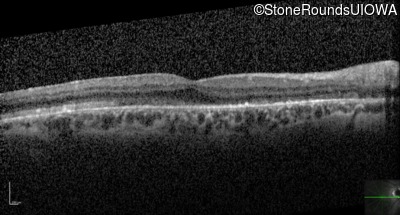

Optical Coherence Tomography - Right - 20/100 +1

Exemplar / OCT Stack